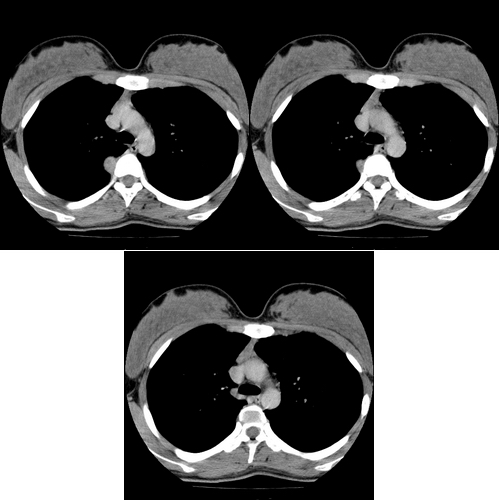

患者 女 18岁,体检无意中发现纵隔病灶,现上传,请会诊.该患者结核菌素实验为强阳性,血沉正常.双肺未见异常.

右后纵隔脊柱旁广基地与胸壁的类圆形病灶,外缘光滑,增强扫描有较明显的强化,未见相应椎体的椎间孔增宽。

定位:肺外,后纵隔病变。

定性:神经源性肿瘤。

没肺窗啊,想必肺窗是正常的吧.ct平扫见右上后纵隔胸椎旁类圆形肿块,内未见钙化,+c后见肿块轻-中等度强化,其前部有少许低密度区.邻近骨质未见破坏.ppd强阳性,但病变不太象结核.后纵隔肿瘤以神经源性多见.不知是否.准确定性难啊.等待结果.

次则需要注意为局限性良性胸膜间皮瘤的可能性--主动脉弓层面胸椎椎体前缘纵隔胸膜增厚,椎体右侧脊肋关节处壁胸膜也有增厚,肿瘤位于二者之间并与之相连。

ct平扫见右上后纵隔胸椎旁类圆形肿块,内未见钙化,+c后见肿块轻-中等度强化,其前部有少许低密度区.邻近骨质未见破坏.ppd强阳性,但病变不太象结核.后纵隔肿瘤以神经源性多见.支气管或食管囊肿不能除外.等待结果.

椎间孔未见明显增大,其增强动脉期似见一动脉伸入肿块内,故先考虑肺外型肺隔离症(尽管此处不是好发部位),支气管囊肿不 除外。